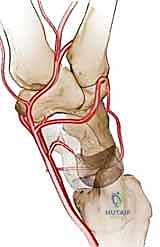

العظم الهلالي (Lunate Bone): حجر الزاوية

يقع العظم الهلالي في الصف القريب، محصوراً بين العظم الزورقي (Scaphoid) والعظم المثلثي (Triquetrum). سُمي بالهلالي نظراً لشكله الذي يشبه الهلال. وظيفياً، يلعب العظم الهلالي دوراً محورياً في توزيع القوى الميكانيكية (الأحمال) من اليد إلى الساعد. يُقدر أن حوالي 50% من القوة الضاغطة التي تعبر الرسغ تمر مباشرة عبر العظم الهلالي إلى عظمة الكعبرة.

التروية الدموية: نقطة الضعف القاتلة

السبب الجذري لمرض كينبوك يكمن في التروية الدموية الفريدة (والهشة أحياناً) للعظم الهلالي. تتلقى معظم العظام الدم من عدة أوعية دموية تدخل من اتجاهات مختلفة. ومع ذلك، في حوالي 20% إلى 30% من البشر، يتلقى العظم الهلالي إمداده الدموي من وعاء دموي واحد فقط (Single Volar or Dorsal Artery). إذا تعرض هذا الوعاء الدموي الوحيد للانسداد، أو التمزق بسبب صدمة، أو الضغط المستمر، فإن العظم يُحرم من الأكسجين والمواد المغذية، مما يؤدي إلى بداية عملية النخر (موت الخلايا العظمية).

إعادة الدم وحده قد لا يكون كافياً إذا استمر الضغط الميكانيكي الهائل على العظم الهلالي الهش. يجب "تخفيف الحمل" (Offloading) عن العظم الهلالي لكي يشفى بسلام.

العظم الكبير (Capitate) هو أكبر عظام الرسغ ويقع مباشرة فوق العظم الهلالي. القوة المركزية لليد تنتقل من العظم الثالث في المشط، إلى العظم الكبير، ثم تصطدم مباشرة بالعظم الهلالي.

4. النتيجة الميكانيكية: من خلال تقصير العظم الكبير، يتم نقل مسار توزيع القوة (Load Shift) بعيداً عن العظم الهلالي الضعيف، وتوجيهه نحو العظم الزورقي والعظام الأخرى. هذا الإجراء يمنح العظم الهلالي "مساحة للتنفس" والشفاء دون أن يتم سحقه تحت ضغط حركة اليد.